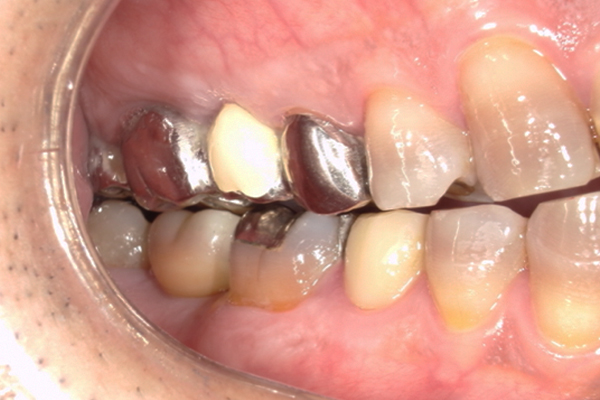

| 主訴 | 奥歯で噛めない、顎が痛い |

|---|---|

| 治療内容 | 奥歯のインプラント治療、前歯・奥歯の被せ物治療 |

| 治療期間 | 6ヶ月 |

| 治療費 | 350万円 |

| 治療リスク | 被せ物をつけた初期の段階で歯がしみることがある(時間とともに改善する) インプラント治療後に3日程度痛みと腫れを伴うことがある |